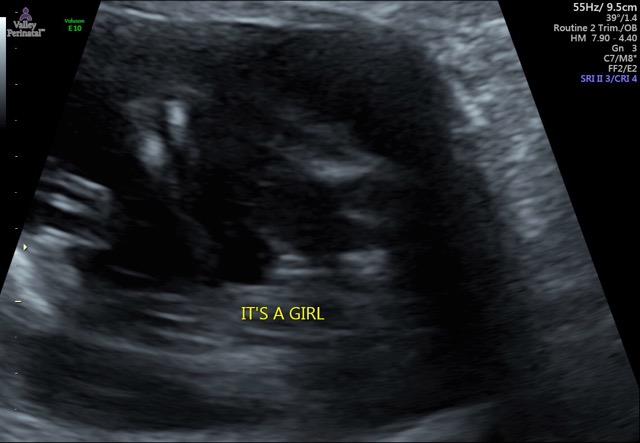

It’s a Girl!!!! Just found out 😁 but also got some bad news my babygirl might have a heart defect I cried so hard when they told me all her organs where flipped around not in the right spot I’m praying she’s ok go back in 4 weeks and will know for sure